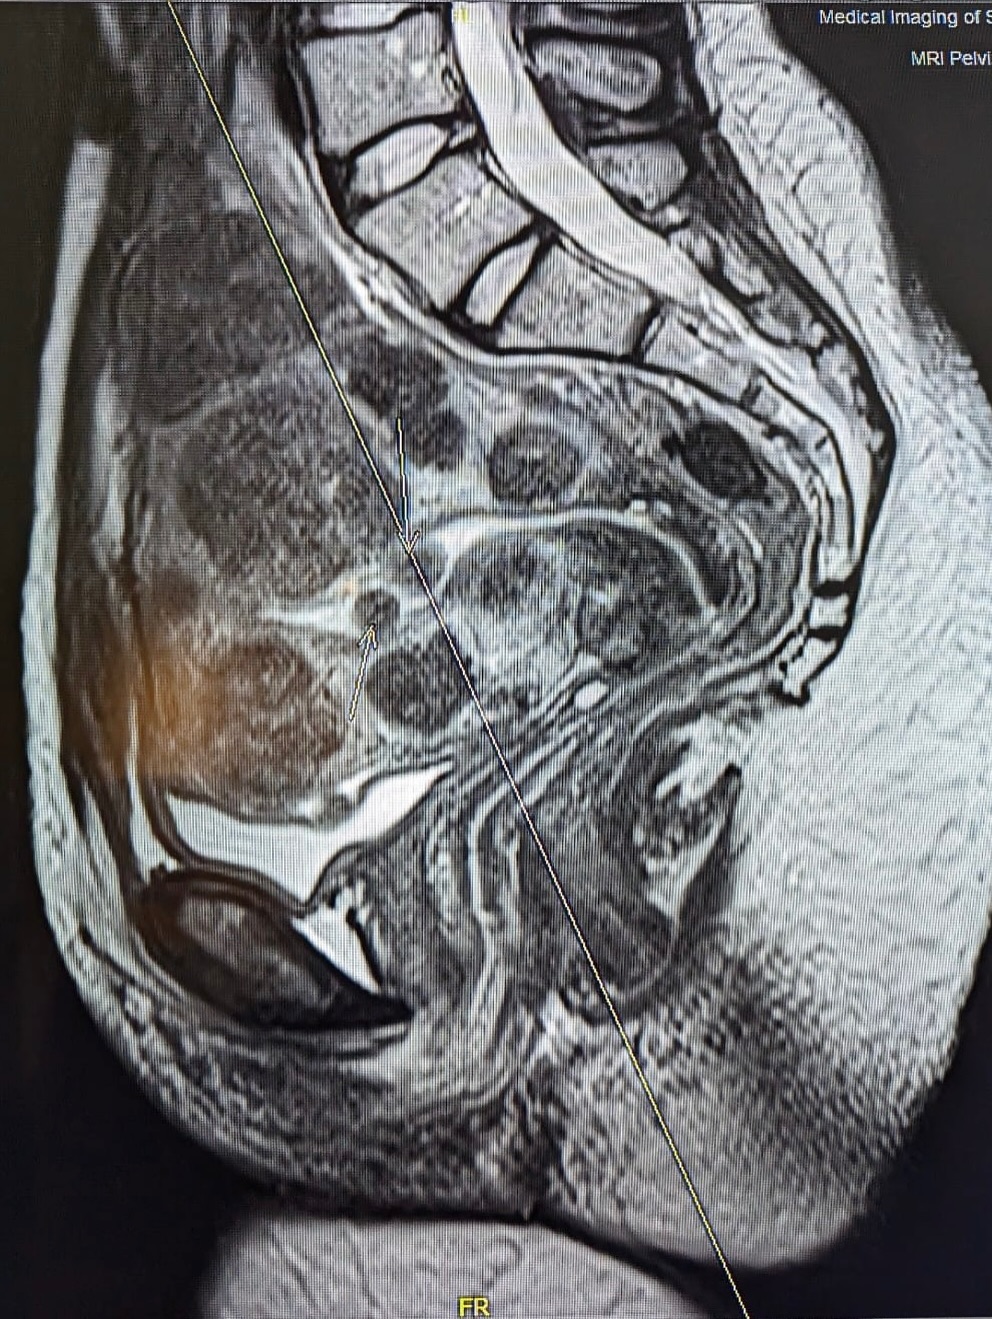

The actress shared her MRI scans alongside the image, offering an unflinching look at a condition she describes as “not a rare story, it is just a rarely told one.“

In a striking visual accompanying her message, Nyong’o is pictured holding 77 fruits a symbolic representation of each fibroid she has carried. “Over the course of my lifetime, I have carried 77 uterine fibroids: 25 surgically removed, and more than 50 still growing inside me today, the largest the size of an orange,” she revealed.

Uterine fibroids are non-cancerous growths in the uterus that affect an estimated 70-80 percent of women by age 50. Despite their prevalence, the condition remains under-researched and under-funded, with many women suffering in silence due to stigma or lack of awareness.